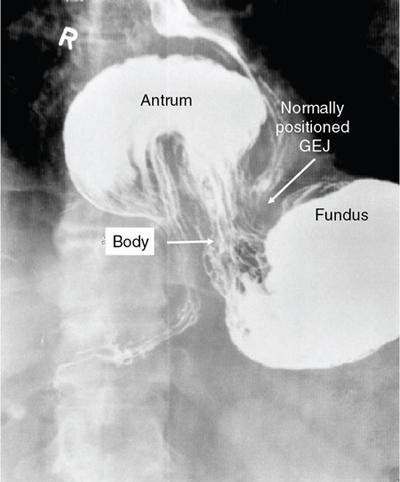

Swarup Nellore, Soumil Vyas, Ujwal Bhure, Ankit Jain, Richa Kothari, Daksh Mehta, Divya Kantesaria, Disha Lokhandwala, Karthik Ganesan The stomach is the most dilated portion of the gastrointestinal tract positioned between the oesophagus and the small intestine occupying the epigastrium, left hypochondrium and umbilical regions of the abdomen performing a multitude of functions including storage and mixing of food and controlling the passage of food into the intestine. Anatomically, the stomach is divided into the following parts (Fig. 8.2.1): the gastric cardia is the portion immediately adjoining the oesophageal opening into the stomach. The fundus is the dome-shaped part above the horizontal plane of the cardiac orifice which undergoes receptive relaxation and is the site of the autonomic pacemaker. The body is the largest part of the stomach extending from the cardiac orifice to the level of incisura angularis (notch like bend in the mid lesser curvature) containing majority of parietal cells (which secrete hydrochloric acid), chief cells (pepsinogen) and enterochromaffin-like cells (ECL). The pylorus is the tubular distal portion of the stomach which is further divided into the gastric antrum and pyloric canal. The pyloric antrum containing G-cells producing gastrin extends from the incisura angularis up to the pyloric sphincter which is an anatomical sphincter formed by concentric thickening of the circular muscle coat and encircles the narrow-slit like pyloric canal. The left dome of diaphragm and oesophagus lie superior to the stomach while the greater omentum and pancreas lie inferiorly. Spleen and liver lie on either side laterally while the transverse mesocolon is located inferolaterally. Diaphragm, greater omentum, left lobe of liver and anterior abdominal wall are anteriorly related to the stomach and contents of lesser sac including pancreas, spleen, splenic artery, transverse mesocolon, left kidney and adrenal gland lie posteriorly. The stomach is embryologically derived from the primitive foregut and is suspended anteriorly by the ventral mesogastrium and posteriorly by the dorsal mesogastrium. During development as the stomach rotates, the peritoneum grows and condenses to form perigastric ligaments, which contain blood vessels, lymphatics, lymph nodes, nerves and fat. The liver forms in the ventral mesogastrium, which develops into the falciform ligament, gastrohepatic ligament (GHL) and hepatoduodenal ligament (HDL). The spleen and pancreas form within the dorsal mesogastrium, which fuses with the posterior abdominal wall to form the gastrocolic ligament (GCL), gastrosplenic ligament (GSL) and splenorenal ligament (SRL). The perigastric ligaments are identified anatomically by the vessels contained in them (Fig. 8.2.2). The gastric cardia and lesser curvature of the stomach are attached to the inferior surface of liver by the lesser omentum by the gastrohepatic ligament respectively which contains the left and right gastric vessels. The inferior free edge of the gastrohepatic ligament extends inferiorly as the hepatoduodenal ligament between the porta hepatis and proximal duodenum gastrophrenic ligament extends between the stomach and the left hemidiaphragm. The gastrocolic ligament identified by the left and right gastroepiploic vessels, connects the greater curvature of the stomach to the anterior surface of the transverse colon. This ligament extends inferiorly as the greater omentum which is a double-layered peritoneum forming a drape anterior to the bowel loops. The gastrosplenic/lienogastric ligament bridges the posterolateral wall of the fundus and greater curvature along the proximal body of the stomach to the splenic hilum and contains the short gastric vessels. The gastrosplenic ligament is contiguous with the lienorenal ligament and both these structures constitute the lateral boundary of the lesser sac. Macroscopically the stomach shows a thick vascular mucosal lining in the form of longitudinal folds called gastric rugae. Microscopic layers of the stomach include mucosa, submucosa, muscularis externa and serosa. The mucosa includes surface mucus cells with simple columnar epithelium, gastric pits, gastric glands, lamina propria and muscularis mucosa. Submucosa includes connective tissue with submucosal Meissner’s plexus. Muscularis externa comprises three smooth muscle layers (longitudinal, circular and oblique) and Auerbach myenteric plexus. The outermost layer called serosa consists of loose connective tissue and visceral peritoneal lining. The arterial supply of stomach is constituted by the branches of celiac artery predominantly in the form of two anastomotic arcades along the lesser and greater curvature. Left gastric artery, a direct branch of the celiac trunk supplies the upper part of the lesser curvature while the lower part is supplied by the right gastric branch of the common hepatic artery arising at the upper border of pylorus. The left gastroepiploic artery, a branch of splenic artery, supplies the upper part of greater curvature and the inferior portion is supplied by the right gastroepiploic artery which is a branch of the gastroduodenal artery. The fundus additionally receives few small short gastric branches from the splenic artery. The veins follow the arteries in their nomenclature. Left and right gastric vein show direct drainage into the portal vein. The splenic vein derives flow from the short gastric and left gastroepiploic vein whereas the right gastroepiploic vein drains into the superior mesenteric vein. Pylorus can be surgically delineated by the prepyloric vein of Mayo lying on its anterior surface. Intrinsic nerve supply consists of the myenteric plexus of Auerbach and submucosal plexus of Meissner. Extrinsic nerve supply consists of sympathetic and parasympathetic components. Sympathetic nerve supply arises from T5 to T9 spinal cord segments supplying the celiac plexus via the greater splanchnic nerve. The plexuses then travel along the respective branches of celiac artery supplying the stomach. Parasympathetic nerve supply is derived from oesophageal plexus of vagus dividing into two vagal trunks. Right (posterior) vagus gives off the posterior gastric branch also called the criminal nerve of Grassi supplying the cardia and fundus of stomach. Right vagus then gives off a celiac branch and continues along lesser curvature of stomach as the posterior gastric nerve of Latarjet supplying the antrum, body and pylorus. Left (anterior) vagus gives off a hepatic branch then continues along the lesser curvature as the anterior nerve of Latarjet supplying the antrum, body and pylorus. Crow’s feet innervation to antropyloric area are important surgical landmarks preserved during highly selective vagotomy receiving branches from both major nerve trunks (anterior and posterior) at the incisura angularis. Anatomical lymphatic drainage is divided into three areas. Area I is the superior two-thirds of stomach draining via the nodes along left and right gastric vessels into the aortic nodes. Area II includes the right two-thirds of the inferior one-third which drains through the nodes along right gastroepiploic vessels via the subpyloric nodes into aortic nodes. Area III includes left one-third of greater curvature draining via short gastric and splenic nodes into suprapancreatic nodes and ultimately into aortic nodes. Gastric lymph node stations are divided into 4 levels with 16 lymph node stations: Paraesophageal nodes below the diaphragmatic hiatus (17) and above the diaphragmatic hiatus (18) are also included. The stomach first appears as a fusiform dilatation in the distal endodermal foregut in the 4th week of embryonic life. The dorsal and ventral mesogastrium suspend the developing stomach to the respective abdominal walls. Preferential growth along the dorsal border of the developing stomach leads to the formation of a convex dorsal border (greater curvature) and a concave ventral border (lesser curvature). The stomach subsequently undergoes a sequence of rotations. The first (90 degrees) clockwise rotation occurs around the longitudinal axis which brings the lesser curvature to the right and greater to the left. This rotation also brings the dorsal mesogastrium towards the left and ventral to the right creating a space behind the stomach called as the lesser sac or omental bursa. The second clockwise rotation occurs around the anteroposterior axis, with the caudal or pyloric part moving upwards and to the right while the cephalic or cardiac portion moves towards the left and slightly downward causing the stomach to assume its final anatomic position. This rotation causes the dorsal mesogastrium to bulge downwards and grow further to eventually become a double-layer apron called the greater omentum. The developing liver divides the ventral mesogastrium into the falciform ligament extending from the ventral abdominal wall to the liver with its lower free edge forming the ligamentum teres, the visceral peritoneum surrounding the liver and the lesser omentum with its two parts – the hepatogastric ligament and hepatoduodenal ligament. The dorsal mesogastrium gives rise to the redundant greater omentum, gastrocolic ligament, gastrosplenic ligament and lienorenal ligament. These perigastric ligaments help us in deciphering patterns of the spread of gastric malignancies and in taking decisions regarding their management and prognostication. These will be further explained in detail under the section of gastric malignancies. An abdominal radiograph is often the initial imaging test for evaluation of acute abdominal pain. The gastric bubble is seen below the left hemidiaphragm in situs solitus. Presence of gastric outlet obstruction may show a distended stomach with gasless small bowel. Hollow visceral perforation is diagnosed by free air seen under domes of diaphragm. Also, the presence and position of various tubes like the nasogastric tube can be confirmed using a radiograph. A fluoroscopic upper gastrointestinal (GI) examination is the radiological study of oesophagus, gastro-oesophageal junction, stomach, duodenum up to duodenojejunal junction by oral administration of contrast. Barium sulphate is a good contrast medium for GI studies as it is radio-opaque, non-absorbable, inert to tissues and can be used for double-contrast studies. Patient should be nil by mouth at least 4 hours prior to the examination. In a single contrast examination, the emphasis is on mucosal relief, luminal distention with contrast material and compression. In the erect position, a small amount of contrast is given to swallow while the oesophagus is visualized under fluoroscopy. The table is then made horizontal and the patient is rotated in a clockwise manner as seen from the foot end of the patient, thus ensuring good coating of the stomach mucosa. Mucosal relief images are then obtained in supine and prone positions to demonstrate the mucosal fold pattern and possible filling defects. After giving some more contrast, the patient is turned oblique with the right side dependent and spot images of the duodenal cap and C loop are taken both in distended and empty states. The patient is again positioned erect and more images of duodenal cap and loop are taken. Further contrast is given to optimally distend the lumen and assess for possible contour abnormalities, wall rigidity and strictures. Compression techniques help assess for filling defects and lesions, in the compressible areas of the stomach. Images are taken in multiple positions – supine, prone, right anterior oblique, right lateral, left posterior oblique in recumbent and right anterior oblique in erect position. Gastric peristalsis and emptying can be observed at fluoroscopy. Advantages of the single contrast technique are that it can be performed quickly, well-tolerated and requires less patient cooperation as compared to double-contrast studies. It can even be performed in physically debilitated patients. Barium is contraindicated in suspected cases of perforation, aspiration, fistula or recent GI biopsy. Single contrast examination can be performed using water-soluble iodinated contrast media in these cases and immediate postoperative patients. Earlier, ionic contrast like Gastrograffin was used. However, due to its high osmolarity, nowadays, non-ionic contrast is preferred as it causes less electrolyte imbalance due to its low osmolarity. Also, it delineates the GI tract very well due to less dilution. Double-contrast studies provide better evaluation of the mucosa than do single-contrast studies. Here, the emphasis is on coating the mucosa with barium and distending the lumen with gas. A well-performed double-contrast study is biphasic and also incorporates some single-contrast techniques. The initial part of the examination is the same as a single contrast examination to obtain the mucosal relief images. Then, gas-forming powder that produces carbon dioxide within the stomach lumen is given with more barium. With the double-contrast technique, the mucosa is coated with a high-density barium suspension and the lumen distended with gas. The patient is rotated in a clockwise manner as seen from the foot end of the patient, thus ensuring good coating of the stomach mucosa. Spot images of the distended stomach are taken followed by the duodenal cap and loop in oblique right-side dependent position. Patient is brought back to erect position erect and more images of stomach, duodenal cap and loop are taken. Further contrast is given to distend the lumen. Residual fluid or food debris in the stomach impairs stomach coating, and lack of adequate coating may preclude visualization of lesions. In addition, optimal gaseous distention is important as underdistention will cause a false appearance of abnormally thickened, and overdistention can obliterate abnormal folds. With normal gastric anatomy, the gastric fundus is best visualized in the upright left-posterior-oblique position, the body in the supine anteroposterior position and the antral-pyloric region in the supine left-posterior-oblique position. The normal gastric mucosal surface should be smooth on double-contrast studies. Areae gastricae appear as reticular networks of polygonal tufts which, owing to the presence of barium in the narrow intervening grooves, are coated with white lines. These are seen most often in the antrum or body of the stomach but can also be seen in the fundus. Areae gastricae are identified on double-contrast studies in 70% of patients and are seen more often in elderly patients. Polygonal tufts should normally range in size from 2 to 3 mm in the antrum and 3 to 5 mm in the body and fundus. Normal gastric folds are more prominent in the proximal to mid stomach and more undulating along the greater curvature as compared with the lesser curvature. Antral folds should be typically effaced with the double-contrast technique. Gastric cardia is characterized by three or four stellate folds radiating from a central point at the gastro-oesophageal junction; this is known as the cardiac rosette and is best visualized in the supine right-lateral position. Ultrasonography (USG) is the modality of choice to visualize hypertrophic pyloric stenosis in infants. Although USG does not play much of a role in adults for imaging of stomach due to reflection of sound waves by air, luminal distension with water may enable to identify mucosal – submucosal pathologies and to assess perigastric relationships in pathologies. CT can not only evaluate the location and anatomy of the stomach, but also provide additional information about the relationship of the stomach to surrounding structures. An optimal CT examination of the stomach includes good stomach distension with a well-visualized wall. Gastric distention can be achieved by the oral administration of negative or positive luminal contrast. Positive contrast agents include a 1%–2% barium suspension or a 2%–3% solution of a water-soluble iodinated contrast agent. Water-soluble agents should be used in cases of suspected perforation. Positive agents provide a bright lumen with better identification of luminal encroachment or diverticula but may limit detailed evaluation of gastric wall enhancement. Positive contrast also may not mix well with gastric contents, producing a pseudotumor appearance. On the other hand, neutral or negative contrasts agents, usually water, produce a low attenuation lumen which allows for more detailed evaluation of the gastric wall and its enhancement pattern following intravenous contrast and is preferred for three-dimensional imaging. Multidetector CT with thin collimation allows for postprocessing in any orthogonal plane. The CT data of the stomach can be manipulated to simulate endoscopic images (virtual gastroscopy). This display technique accentuates the stomach wall and folds. Prior to evaluating the stomach with CT, oral contrast is administered at repeated intervals as well as immediately prior to scanning. Multiphasic scanning after intravenous contrast may be employed at 25–35 seconds (late arterial), 55–75 seconds (venous phase) after contrast injection. Normally, the gastric wall may enhance to approximately 120 Hounsfield Units after intravenous contrast administration. The mucosa may enhance more than the relatively lower-attenuation muscularis propria. Abnormal enhancement of the wall can highlight pathologic processes. The CT appearance of the stomach also depends upon the degree of distention. When well distended, the body and fundus is less than 5 mm thick, though the normal antrum may appear slightly thicker. The presence and pattern of wall enhancement, degree and location of wall thickening, and length of an involved segment may be assessed. Comprehensive MRI examination of the stomach and duodenum by the combined use of T2-weighted single-shot and T1-weighted gradient echo (GRE) – with and without fat suppression, and gadolinium-enhanced 3D GRE helps to detect the spectrum of gastric diseases on MRI. These sequences minimize artefacts from bowel peristalsis, increase the sensitivity of detection of peritoneal and serosal disease by suppressing the high signal of intra-abdominal fat, widen the dynamic range of abdominal tissue signal intensities and distinguish between intraluminal bowel contents and bowel wall. The gastric rugae are well seen on T2-weighted single-shot spin-echo images and their enhancement appears as bands of enhancing tissue arranged perpendicular to the external contour of the gastric wall. The normal gastric wall enhances more intensely than other segments of bowel on immediate postgadolinium SGE images. Water is frequently used as an oral contrast agent when imaging the upper GI segment-stomach and duodenum. Noninvasive dynamic study for assessment of gastric motor function and wall motility can also be done using MRI for diagnosis of gastroparesis. Gastric emptying scintigraphy (GES) is a well-established radionuclide procedure to evaluate patients with suspected gastric motility disorder, more so for non-invasive assessment of gastroparesis in patients with symptoms of postprandial fullness, nausea, vomiting, abdominal pain, bloating, early satiety, loss of appetite, as well as weight loss. Gastroparesis, commonly seen in diabetics, is a condition that affects the normal spontaneous movement of the gastric muscles, leading to impairment of gastric motility, because of which the stomach cannot empty itself of food in a normal fashion and time. GES can also provide useful information with regards to assessment of impaired gastric motility in patients with GERD (gastro-oesophageal reflux disease) unresponsive to routine therapy, diabetics with poor glycemic control, and also in patients with colonic inertia who are being considered for colectomy (since benefits of colectomy are mitigated in patients with concurrent impaired gastric emptying). On the other hand, GES is also useful for assessment of rapid gastric emptying (GE), which is a major factor in dumping syndrome, often seen post peptic ulcer surgery, with or without vagotomy. The solid or liquid component of a meal is radiolabelled with a radiopharmaceutical, which is consumed by the patient and subsequently measured gastric radioactive counts by scintigraphy correlate with the volume of the meal remaining in the stomach. Solid-phase GES is used for the evaluation of gastric motility disorder/gastroparesis. Liquid-phase gastric emptying is generally not clinically useful since it is often in the normal range in spite of deranged emptying for solids even with severe gastroparesis. The preferred radionuclide meal for the gastric emptying scintigraphy includes egg-white radiolabelled with 0.5–1.0 mCi of Technetium-99m (99mTc) [approximate caloric value of 255 kcal]. Two large eggs (egg-whites), two slices of bread, fruit jam, water (120 mL approximately), and the radiopharmaceutical (0.5–1.0 mCi of 99mTc–sulphur colloid). For patients allergic, to eggs, alternative meals like oatmeal or Liquid Ensure nutrient supplement can be used. Reporting should include the percentage of radiotracer retained in the stomach at defined time intervals. The normal reference values for comparison are as follows: Grading the severity of the delay in gastric emptying based on gastric retention at 4 hours of the study: Gastro-oesophageal reflux (GER) is a common condition in infants and children, wherein there is reflux of stomach contents into the oesophagus, due to possible incompetence of gastro-oesophageal sphincter, which can lead to development of symptoms like regurgitation, heartburn, cough and dyspepsia. Children can present with recurrent respiratory infections, iron deficiency anaemia and failure to thrive. It is often a self-limited process in infants and children which usually resolves by 12–18 months of age. On the other hand, gastro-oesophageal reflux disease (GERD) is a chronic pathological process which can be troublesome. Scintigraphic evaluation of gastro-oesophageal reflux, popularly known as ‘milk scan’, is an established imaging modality and has sensitivity of 75%–100%. This radionuclide test for gastro-oesophageal reflux is physiological and quantitative and commonly used for diagnosis in neonates and infants. Four hours fasting is preferred. A liquid meal consisting of formula, milk, or orange juice mixed with the radiopharmaceutical is administered either orally or by nasogastric tube. 99mTc–sulphur colloid. Dose: 0.2 to 1 mCi. After administering the liquid meal and allowing burping, the baby is positioned supine under the gamma camera detector head, including chest and upper abdomen in the field of view. A radioactive marker can be placed at the mouth. Anterior serial dynamic planar images are acquired for around 60 minutes with a framing rate of 5–10 seconds per frame. Delayed anterior static image of the chest may be acquired additionally. The acquired frames are reviewed in cinematic display for visual estimation and to look for reflux of the radiotracer into the oesophagus. Reflux is seen as distinct spikes of radiotracer activity into the oesophagus. For quantitative estimation, the volume of each episode of reflux, frequency of episodes and rate of reflux clearance from the oesophagus are taken into consideration. Percentage of reflux is calculated by drawing an ROI over the oesophageal spike of radiotracer activity and the counts are calculated and expressed as a fraction of the gastric activity counts. Values greater than 5% are suggestive of reflux. Semiquantitative evaluation grades each reflux event: Based on this, four categories can be formulated: The greater the number of high-level reflux events and the longer they last, more severe is the gravity of the problem. Pulmonary aspiration should also be looked for, though the sensitivity of detection is poor. Liquid gastric emptying can be evaluated during the same study up to 2 hours. Normal values for liquid gastric emptying are: Endoscopy is the preferred examination to evaluate for majority of the upper GI symptoms. It is very sensitive in detecting mucosal lesions and simultaneously, biopsies can be taken. In cases of upper GI bleed, endoscopy can not only detect the site and cause of the bleed, but also further treatment like adrenaline/sclerosant injection or ligation can be done. EUS can provide detailed assessment of the 5 layers of the gastric wall and is thought to be the most accurate non-surgical method for local tumour staging (Fig. 8.2.9). For subepithelial (submucosal) gastric lesions, EUS can assess the echogenicity of a lesion, the exact layer of the gastric wall which is involved (accurate T-staging of a tumour) and assess for the presence of blood flow with Doppler ultrasound to help ascertain the likely aetiology. EUS-guided fine needle aspiration may also provide additional diagnostic information. Hiatus hernia is a common positional abnormality of stomach, characterized by herniation of abdominal contents, commonly the gastro-oesophageal junction and stomach, into the mediastinum above the diaphragm through a widened oesophageal hiatus. The oesophageal hiatus is an elliptical opening with complex anatomy formed by the right and left crus of the diaphragm. However, the most common anatomical description is of the right crus splitting into two bundles, the right and left, which form a sling encircling the distal oesophagus and may be reinforced by the left diaphragmatic crus. The distal oesophagus is typically anchored to the oesophageal hiatus by a main restraining structure which is the phrenicoesophageal ligament/membrane (the fascia of Laimer) which is a condensation of endo-thoracic and endo-abdominal fascia and this membrane circumferentially inserts into the oesophageal musculature in close proximity to the squamocolumnar junction (SCJ). The ligament maintains the competence of the oesophageal hiatus and prevents rostral herniation of the gastro-oesophageal junction and stomach. During normal physiological swallowing, the longitudinal layer of the oesophageal muscularis propria contracts with associated oesophageal shortening and stretching of the phrenicoesophageal ligament/membrane resulting in the transient elevation of the oesophagogastric junction and portion of the stomach above the hiatus. At the end of the swallowing mechanism, the elastic recoiling of the phrenicoesophageal ligament/membrane restores the migrated segment to its normal position. With ageing-related wear and tear, the ligament becomes lax with progressive depletion of elastin fibres resulting in proximal migration of the gastro-oesophageal junction and stomach. Other potential risk factors of fibromuscular degeneration are caused by increase in the intra-abdominal pressure as occurs in obesity and pregnancy. The majority of the symptomatic cases of hiatal hernia present with the clinical symptoms of gastro-oesophageal reflux disease (GERD) with most characteristic manifestations of acid regurgitation, heartburn, dysphagia, epigastric or chest pain and even chronic iron deficiency anaemia. Large hernias may also present with early satiety. Conventionally, hiatus hernias are classified into sliding and paraesophageal varieties. The current comprehensive anatomic classification has evolved to include a categorization of hiatal hernias into Types I–IV and is necessary especially regarding the treatment approach, as indications for the surgical method are quite different between sliding and paraesophageal hernias. Majority of hiatus hernias (95%) are sliding hiatus hernias (type I), the remaining type II–IV hernias as a group are referred to as paraesophageal hernias (PEH), with more than 90% of these comprising type III, and the least common being of type II. The assessment of hiatus hernia can be done by various modalities including radiological, manometry and endoscopy studies. The diagnosis of a large hiatus hernia is straightforward, however, identifying a small one is challenging due to mobility of the gastro-oesophageal junction during physiological process like deglutition and respiration. According to the SAGES Guidelines, only those investigations which will alter the clinical management of the patient should be performed. Radiological investigations are usually indicated for diagnosis and presurgical evaluation. Plain chest radiographs demonstrate opacity within the chest typically in the midline overlapping the cardiac shadow or paramedian location (Fig. 8.2.14A), with or without an air-fluid level. Barium swallow radiography is still considered an easy tool for diagnosis of hiatus hernia and provides essential information about the size, location, motility dysfunction, stricture secondary to GERD and stenosis. The evaluation of hiatus hernia requires understanding of anatomical radiographic landmarks like phrenic ampulla, A ring and B ring (or Schatzki’s ring) on a barium study (Fig. 8.2.14B). The phrenic ampulla is a globular structure seen above the diaphragm and below the tubular oesophagus during a contrast swallow. The A ring represents a muscular ring visible at the upper margin of the phrenic ampulla and physiologically corresponds to the highest-pressure zone within the lower oesophageal sphincter, this is often seen as a transient indentation on the oesophageal lumen. The B ring identified in about 15% of individuals, representing the mucosal ring corresponds to the squamocolumnar junction (Z line) and divides the phrenic ampulla into the oesophageal vestibule (A ring to B ring) and the sliding hiatus hernia (B ring to the stomach below the diaphragm). The B ring is a persistent constriction which is not usually not more than 2–3 mm and despite mucosal, can sometimes be symptomatic and require dilatation. By convention, there must be a distance of 2 cm or more between the B ring and the hiatus, to call it a hiatus hernia as physiological migration up to 2 cm is known in normal individuals. Although not reliable, barium studies may also provide information about a short oesophagus, which is identified as a tubular straightened oesophagus with the oesophagogastric junction fixed far above the diaphragm and may be stenotic, the intrathoracic herniated stomach revealing a more elongated funnel/bell – shaped configuration. Cine fluoroscopy provides further additional information about the bolus transit through gastro-oesophageal junction. The major drawbacks of the procedure are non-visualization of B-ring in majority of the cases, radiation exposure, barium/iodine hypersensitivity, contraindication in pregnancy and increase risk of aspiration in paraesophageal hernia causing pneumonitis. Computed tomography (CT) scan is not routinely advised for the primary diagnosis of hiatus hernia but is indicated in cases of suspected complications like volvulus in paraesophageal hernia, obstruction, perforation and strangulation. Multi-slice CT with reconstruction in sagittal, coronal planes and 3D reformations have increased the sensitivity of CT in detection of hiatal hernia. Oesophagogastroduodenoscopy gives added advantage of real-time visual assessment of the mucosa of the oesophagus, stomach and duodenum. The common diagnostic criteria in endoscopic is proximal migration of gastro-oesophageal junction by >2 cm. Endoscopy can also determine the presence of erosive esophagitis or Barrett’s oesophagus. Further, the inability or difficulty of negotiating the scope into duodenum in the presence of a large hiatal hernia is diagnostic of paraesophageal hernia with volvulus. Evaluation of gastric viability is also important in patients undergoing emergency surgery for incarcerated hernias. The disadvantage of the procedure is lack of reproducibility; retching or belching of the patients during examination which can alter the location and anatomy of GEJ and excess air insufflation of the stomach which may exaggerate the size of the hernia. Oesophageal manometry is measured at the level of the diaphragmatic crura, however, manometric landmarks differ from that of barium study and endoscopy, and identified by pressure inversion point. In patients with a paraesophageal hiatal hernia, placement of the manometry catheter across the lower oesophageal sphincter and below the diaphragm can be difficult. The procedure is planned before surgery to exclude motility disorders like achalasia and to verify the integrity of oesophageal peristalsis. pH testing is not essential in the diagnosis of a hiatal hernia, but is necessary for a quantitative analysis of reflux in a case of hernia which can be relieved by antireflux surgery. Confirmation of abnormal gastro-oesophageal reflux on upper endoscopy, or increased oesophageal acid exposure on pH monitoring is necessary prior to operative intervention in patients with a sliding hiatal hernia. Nuclear medicine studies, transoesophageal echocardiogram (TEE) and endoscopic ultrasound (EUS) can also demonstrate hiatal hernias but are not routinely used for diagnosis. The main aim of treatment in symptomatic patient is to reduce the acid reflux. Lifestyle modifications are the first line of management and include weight loss, elevating the head of the bed preferably by 8 inches during sleep, avoidance of meals for atleast 2–3 hours before bedtime and elimination of ‘trigger’ foods. According to the SAGES Guidelines updated in April 2013, the treatment protocols are provided on the basis of types of the hiatus hernia. Type I (sliding) hiatus hernia are usually managed with proton pump inhibitors for 8 weeks, once or twice daily depending on the symptoms. Other alternatives are H2 receptor antagonists and antacids. If the patient is not relieved symptomatically by medication, surgical repair like laparoscopic fundoplication (Nissen or Toupet) can be done. Steps of fundoplication comprise surgically relocating the gastro-oesophageal junction below the diaphragm, maintaining an oesophagogastric angle to prevent gastro-oesophageal reflux, constructing a gastric wrap around the distal oesophagus to support the distal oesophageal sphincter and increase its resting pressure, and finally approximate the diaphragmatic hernia to narrow the widened hiatus. In all symptomatic Type II, III and IV hiatus hernia, surgical repair is strongly recommended as the primary treatment, particularly those with acute obstructive symptoms or which have undergone volvulus. Routine elective repair of completely asymptomatic paraesophageal hernias may not always be indicated and determinants for surgery should include the patient’s age and co-morbidities. These fundoplication surgeries are described later in the text. Gastric volvulus is an uncommon entity and characterized by abnormal rotation of the stomach (usually >180°) along the long or short axis, leading to variable degree of gastric obstruction, which can be of a closed-loop type resulting in strangulation. The exact incidence of gastric volvulus is unclear as patients with a chronic presentation may never be diagnosed.2 Approximately, 10%–20% cases of gastric volvulus occur in children less than 1 year, while the other 80% cases are detected in adults, of which 80%–90% are often encountered in the fifth decade of life.3 No significant predilection is seen with either sex or races. Gastric volvulus can be classified on the basis of aetiology, axis of rotation and duration of onset. While classification based on axis of rotation by Singleton is widely accepted and more relevant to the radiologist, classification based on duration of onset of symptoms is more relevant in clinical assessment. On the basis of axis of rotation (Fig. 8.2.15), gastric volvulus is divided into organoaxial volvulus, mesenteroaxial volvulus and the rarest combined/mixed type. Organo-axial volvulus, by far, the most common type of gastric volvulus, encountered often in the elderly, is characterized by rotation of the stomach along its long axis, that is, cardio-pyloric axis, and resulting in an ‘inverted stomach’ with a horizontal orientation, in the form of anterosuperior displacement of the antrum and posteroinferior rotation of the fundus, so that the greater curvature is displaced superiorly and lesser curvature caudally in the abdomen (Fig. 8.2.16). The site of obstruction in this type of volvulus is at the cardia or at pylorus. It has a higher predisposition towards strangulation and ischaemia. Organo-axial volvulus also shows association with the paraoesophageal hernia or diaphragmatic defects, which allows abnormal movement of the stomach along the long axis. If the degree of rotation is less than 180 degrees, the patient may have an incomplete or partial volvulus which is not completely obstructing and may be asymptomatic; it may be more appropriate to describe it as organo-axial position rather than volvulus. Mesenteroaxial volvulus is less commonly encountered (30%) and accounts for about 29% of cases, is reported more often in young adults or children. It occurs when the stomach rotates around its short (transverse) axis, that is, line connecting the midpoint between the lesser curvature and the greater curvature of the stomach, leading to a vertically oriented stomach, with anterior rotation of the pylorus, antrum and resultant displacement of the antrum above the gastro-oesophageal junction (Figs 8.2.17 and 8.2.18). The site of obstruction is usually at antropyloric region. It is usually not associated with a diaphragmatic defect and is often idiopathic. The third and rarest type of gastric volvulus is the combined type when the stomach shows both rotation along the short and long axes. Based on aetiology of rotation, gastric volvulus can be subdivided into either primary or secondary. Primary gastric volvulus representing 25%–30% of the cases, is more common in the adults. It occurs in the subdiaphragmatic location due to abnormality in the gastric fixation, exclusively because of disruption, laxity or absence of the gastric ligaments which anchor the stomach in place. These ligaments namely the gastrohepatic, gastrocolic, gastrophrenic, gastrosplenic and gastropancreatic ligaments, along with gastro-oesophageal junction and pylorus, provide anchorage and fix the stomach in place intra-abdominally, and prevent abnormal rotation of the mesentery. The primary gastric volvulus usually presents with the mesenteroaxial type of anatomical configuration. Around 70% of patients present with secondary gastric volvulus occurring due to abnormal rotation around the lead point formed by associated disease. The most common association of gastric volvulus is seen with paraoesophageal hiatus hernia. Other causative factors of volvulus include congenital or traumatic diaphragmatic hernia, diaphragmatic paralysis, eventration, connective tissue disorders, previous surgery, adhesions, peptic ulcer, neoplasm, splenomegaly or absence of the spleen and colonic overdistension. On basis of clinical presentation and speed of onset, gastric volvulus can be acute, subacute or chronic. Acute gastric volvulus is a surgical emergency and usually presents with sudden onset epigastric pain, distension, non-bilious vomiting or severe retching, depending on the degree of obstruction. The Borchardt triad of acute volvulus comprises severe epigastric pain and distention, retching but inability to vomit, and difficulty or impossibility of passing a nasogastric tube and may be observed in 70% of cases. Other symptoms include hematemesis due to mucosal sloughing in stomach gangrene or mucosal tear due to retching, dysphagia and dyspnea. Even after prompt treatment, mortality of acute gastric volvulus can be up to 30%–50%, likely secondary to gastric ischaemia, perforation or necrosis resulting from severe gastric obstruction (closed-loop obstruction) causing vascular compromise, making it a life-threatening surgical emergency. Chronic gastric volvulus represents spectrum of diseases from long-standing partially obstructed volvulized stomach with incomplete gastric obstruction on the one side, and intermittent volvulus of stomach with recurrent episode of acute symptoms as the other presentation. Chronic gastric volvulus usually presents with intermittent complaints of vague epigastric pain, non-bilious vomiting, dysphagia or early satiety, dyspepsia and sometimes regurgitation. Due to nonspecific clinical symptoms, diagnosing gastric volvulus is very challenging on the first instance and requires a high clinical suspicion. Diagnostic imaging, along with clinical findings are usually required to achieve the correct diagnosis, and also plays major role in excluding the other common differential diagnosis, like pancreatitis, cholecystitis or pneumonitis etc. The diagnostic modalities useful in suspected cases of gastric volvulus are plain radiographs, upper gastrointestinal contrast (barium) studies, computed tomography and upper gastrointestinal endoscopy. Plain chest and abdominal radiographs may reveal a radiolucent hollow viscus, with or without an air-fluid level, in the chest (when associated with PEH) or upper abdomen. The presence of a nasogastric tube may assist in identifying a malpositioned stomach, and administration of contrast via the nasogastric tube may be confirmatory in this regard. Furthermore, chest radiographs may identify evidence of underlying anatomic abnormalities predisposing to gastric volvulus, including elevated hemidiaphragm due to phrenic nerve palsy or diaphragmatic eventration and rib fractures suggesting prior thoracoabdominal blunt trauma. The plain radiographs may show two air-fluid levels in the antrum and fundus, or a single air bubble with no additional luminal gas in the supine position. A retrocardiac air-fluid level may be seen secondary to hernia and presence of intramural air (gastric emphysema) can be visualized as a radiolucent stripe in the gastric wall. At times a large hiatus hernia may be complicated by volvulus (Fig. 8.2.19). Passage of orally administered contrast like barium can demonstrate the anatomy and also assess the degree of obstruction. As mentioned above, the position of the gastric curvatures and the gastro-oesophageal junction are useful in differentiating the anatomical subtype of volvulus. Computed tomography may be more feasible in an acute emergency setting in order to identify abnormal gastric position, axis and multiplanar reconstructions, especially in the coronal plane, can well elucidate the findings and an associated complication like ischaemia. CT has an overall 90% accuracy in the diagnosis with identification of gastro-oesophageal junction and pylorus lying in close proximity to each other and the transition point at the pylorus known to have 100% sensitivity and specificity. Abnormal antral folds may be seen secondary to the twisting. Stenosis at the neck of the hernia is the CT finding with the second-highest sensitivity (77%–80%) and specificity (94%–97%). CT findings of oedematous or hypoenhancing gastric wall, pneumatosis, pleural effusion or pneumoperitoneum, as indicators of gastric ischaemia are not common but specific when identified. An upper gastrointestinal endoscopy confers both diagnostic and therapeutic benefit, although it may establish the diagnosis in only 28%–45% patients and also, the endoscopic procedure may reduce the volvulus missing the diagnosis by an unwary endoscopist. However, it still remains the best method to detect mucosal ischaemia. Flexible endoscopy also has the advantage of placing a nasogastric tube as it may not be possible with a blind technique at the bedside in the setting of organoaxial volvulus and an obstructed gastro-oesophageal junction. Nasogastric decompression forms the initial management of gastric volvulus with emergent laparotomy or laparoscopy to assess gastric viability, resect gangrenous portion if any and perform de-rotation and gastropexy (fixation of the stomach to the diaphragm and/or the anterior abdominal wall) with or without gastrostomy with repair of secondary factors like paraoesophageal hernia. Erosions are focal shallow areas of ulcerations confined to the epithelium or lamina propria without extending through the muscularis mucosae into the submucosa. NSAIDs are the most common cause of gastric erosions while other incriminated factors include Helicobacter pylori infection, alcohol, viral infections, Crohn’s disease, stress and iatrogenic trauma. Erosions may be visible on double-contrast barium examination obtained with good mucosal coating, as multiple tiny 1- to 2-mm collections of barium, often with a surrounding mound of oedema appearing as a filling defect in the barium pool (Fig. 8.2.20). They are usually located in the gastric antrum and tend to occur along thickened folds.

Gastric volvulus